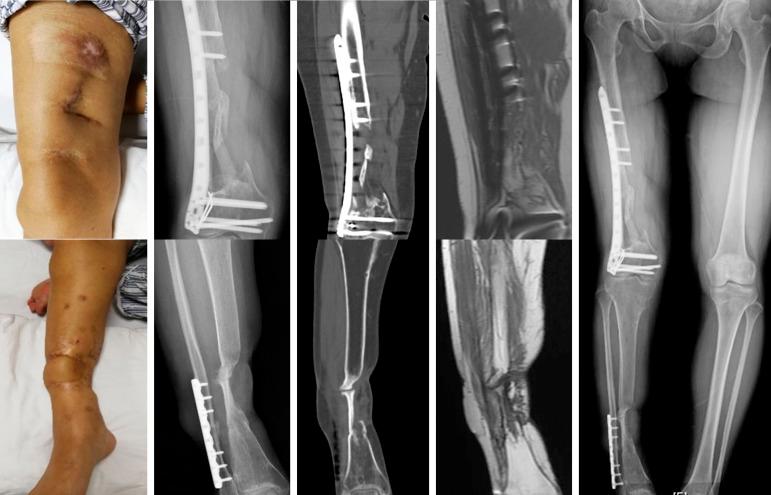

This study reported the case of a 42-year-old woman with traumatic ipsilateral critical bone defect of right femur and tibia after a motor accident. Three-dimensional (3D) printed porous titanium scaffolds were innovatively used to reconstruct this challenging situation. The initial stability was safe enough for early exercise and partial weight bearing. The 26-month follow-up showed osseous integration of the prosthesis-bone interface with short-term satisfactory clinical result.

本研究报告了一例车祸后右侧股骨和胫骨同侧严重创伤性骨缺损的 42 岁女性病例。创新性地使用了三维(3D)打印多孔钛支架来重建这种具有挑战性的情况。初始稳定性足以确保早期运动和部分负重的安全性。26 个月的随访显示假体-骨界面具有骨整合,短期临床效果满意。